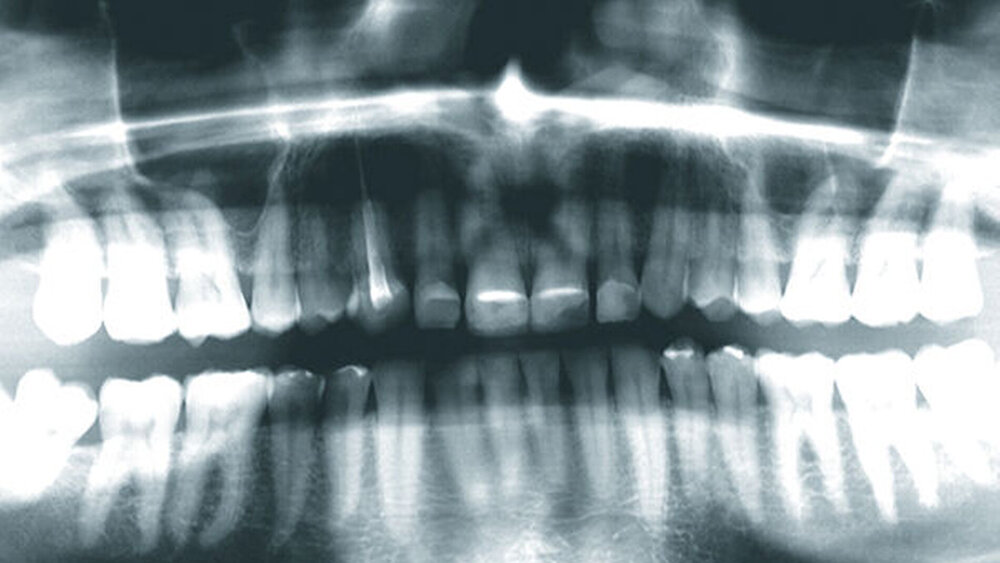

2015 stellte sich ein 47 Jahre alter Mann mit Schmerzen im TMG (Temporomandibulargelenk) vor. Er hatte außerdem ein ästhetisches Anliegen, da ein Stück vom Veneer eines mittleren oberen Schneidezahns abgebrochen war (Abb. 1–3). Die klinische und radiografische Analyse (Abb. 4) ergab einen Verlust der Bisshöhe und der Zahnsubstanz aufgrund von Bruxismus.